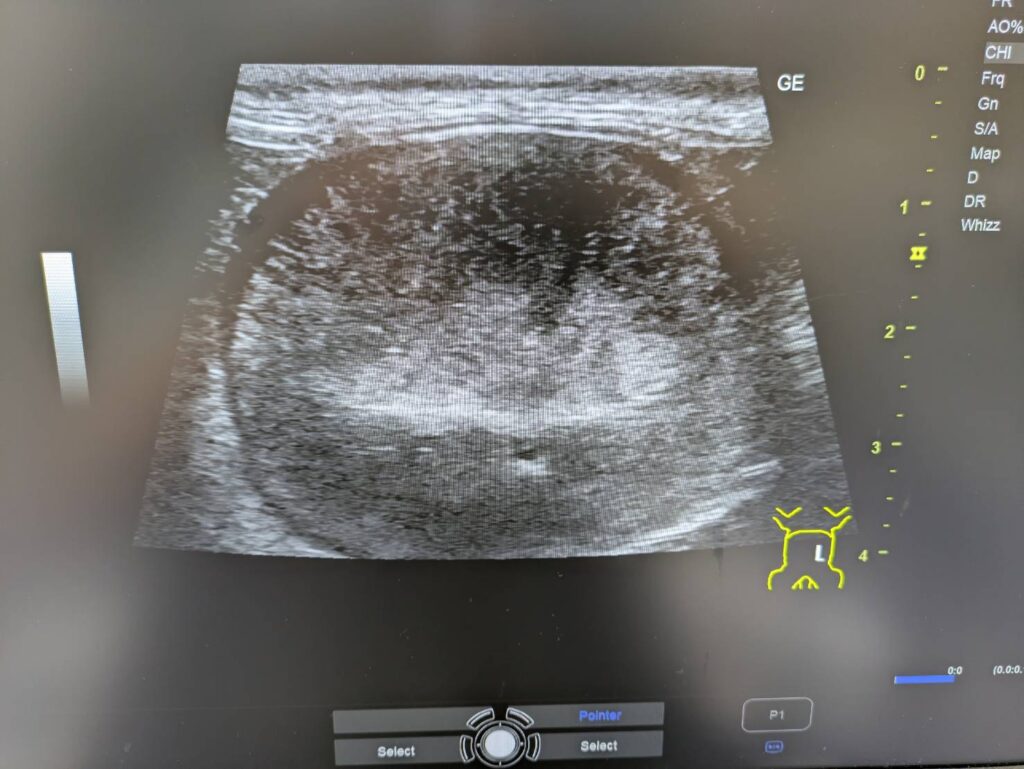

腹部超音波検査にて左の腎臓がこんな感じでした。

少し腎臓の大きさが肥大しているように見えるのと

腎臓の被膜下に黒い領域を認め

そこに向かって、皮質に放射状に線が入っているようにも見えます。

腎臓のリンパ腫が最も疑わしいのかなと考えております。